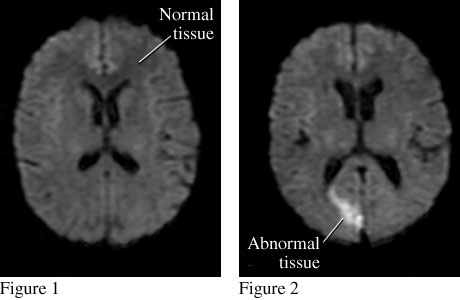

Stroke MRI